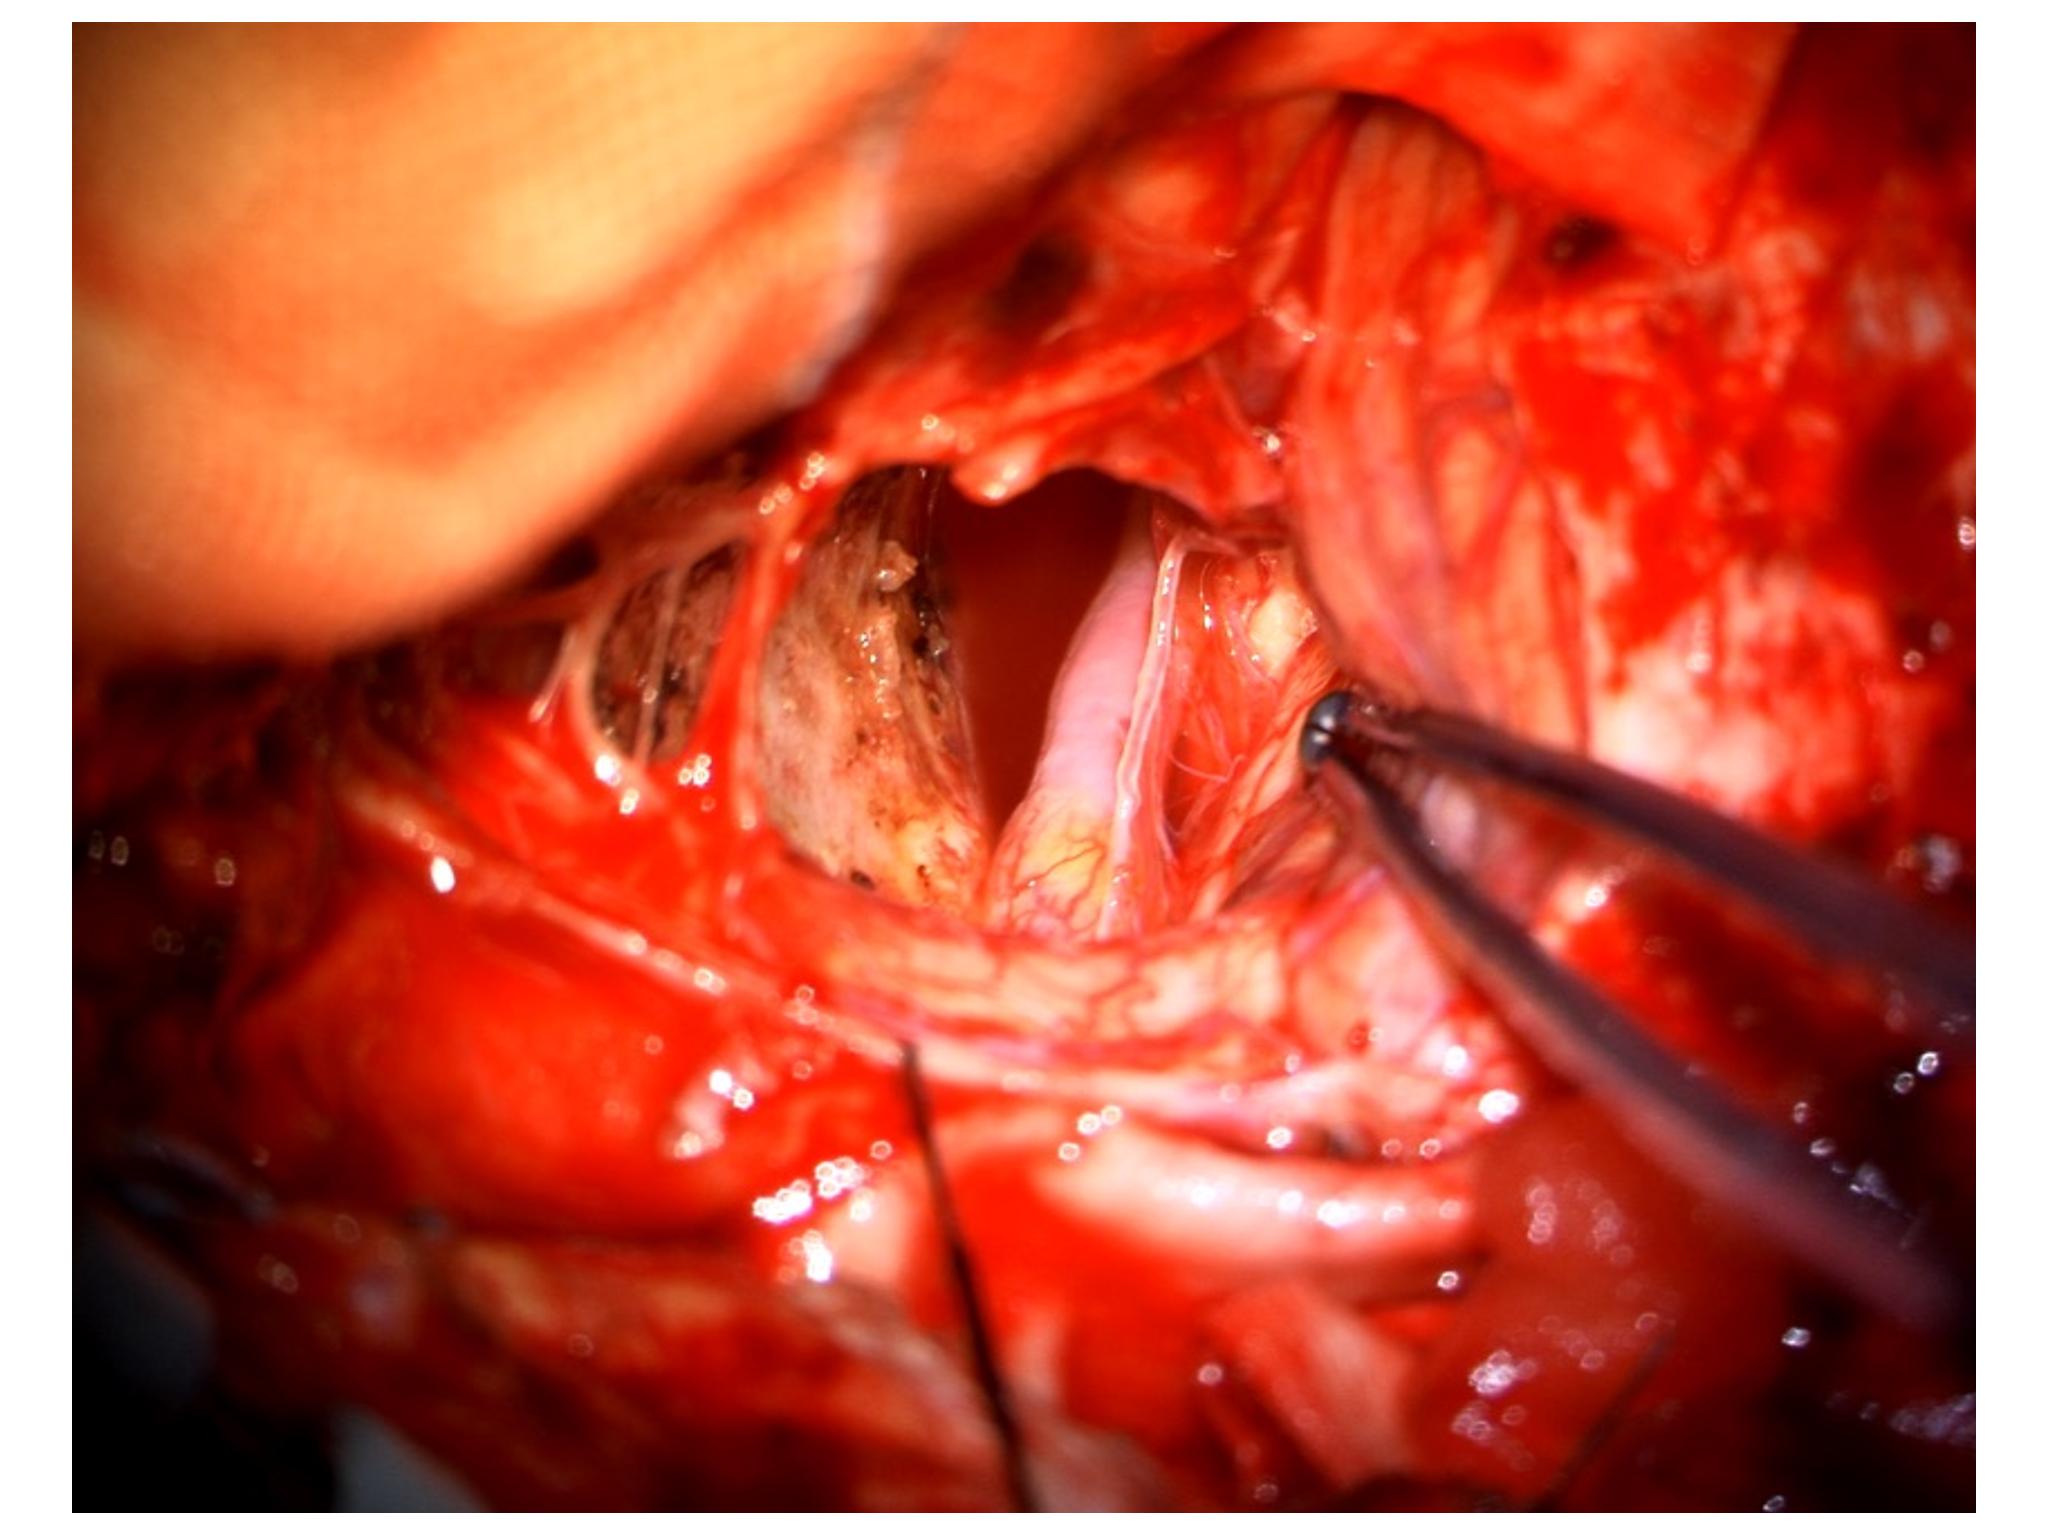

汇报一例后颅底肿瘤手术。为枕骨大孔巨大腹侧型脑膜瘤,该患者高龄,同时合并肺Ca,术前2周急性加重,枕骨大孔疝前期表现,术前已有延髓压迫及后组颅神经麻痹表现。经详细评估后采用远外侧经髁窝入路,最大化显露,重点保护延髓、后组颅神经,尽可能“零骚扰”。术中肿瘤质地韧,血供一般,与肿瘤上极与后组颅神经黏连紧密,最终99%切除,残留约1%,术后顺利康复出院,无新发症状,为后续进行肺部病变化疗创造有利条件。